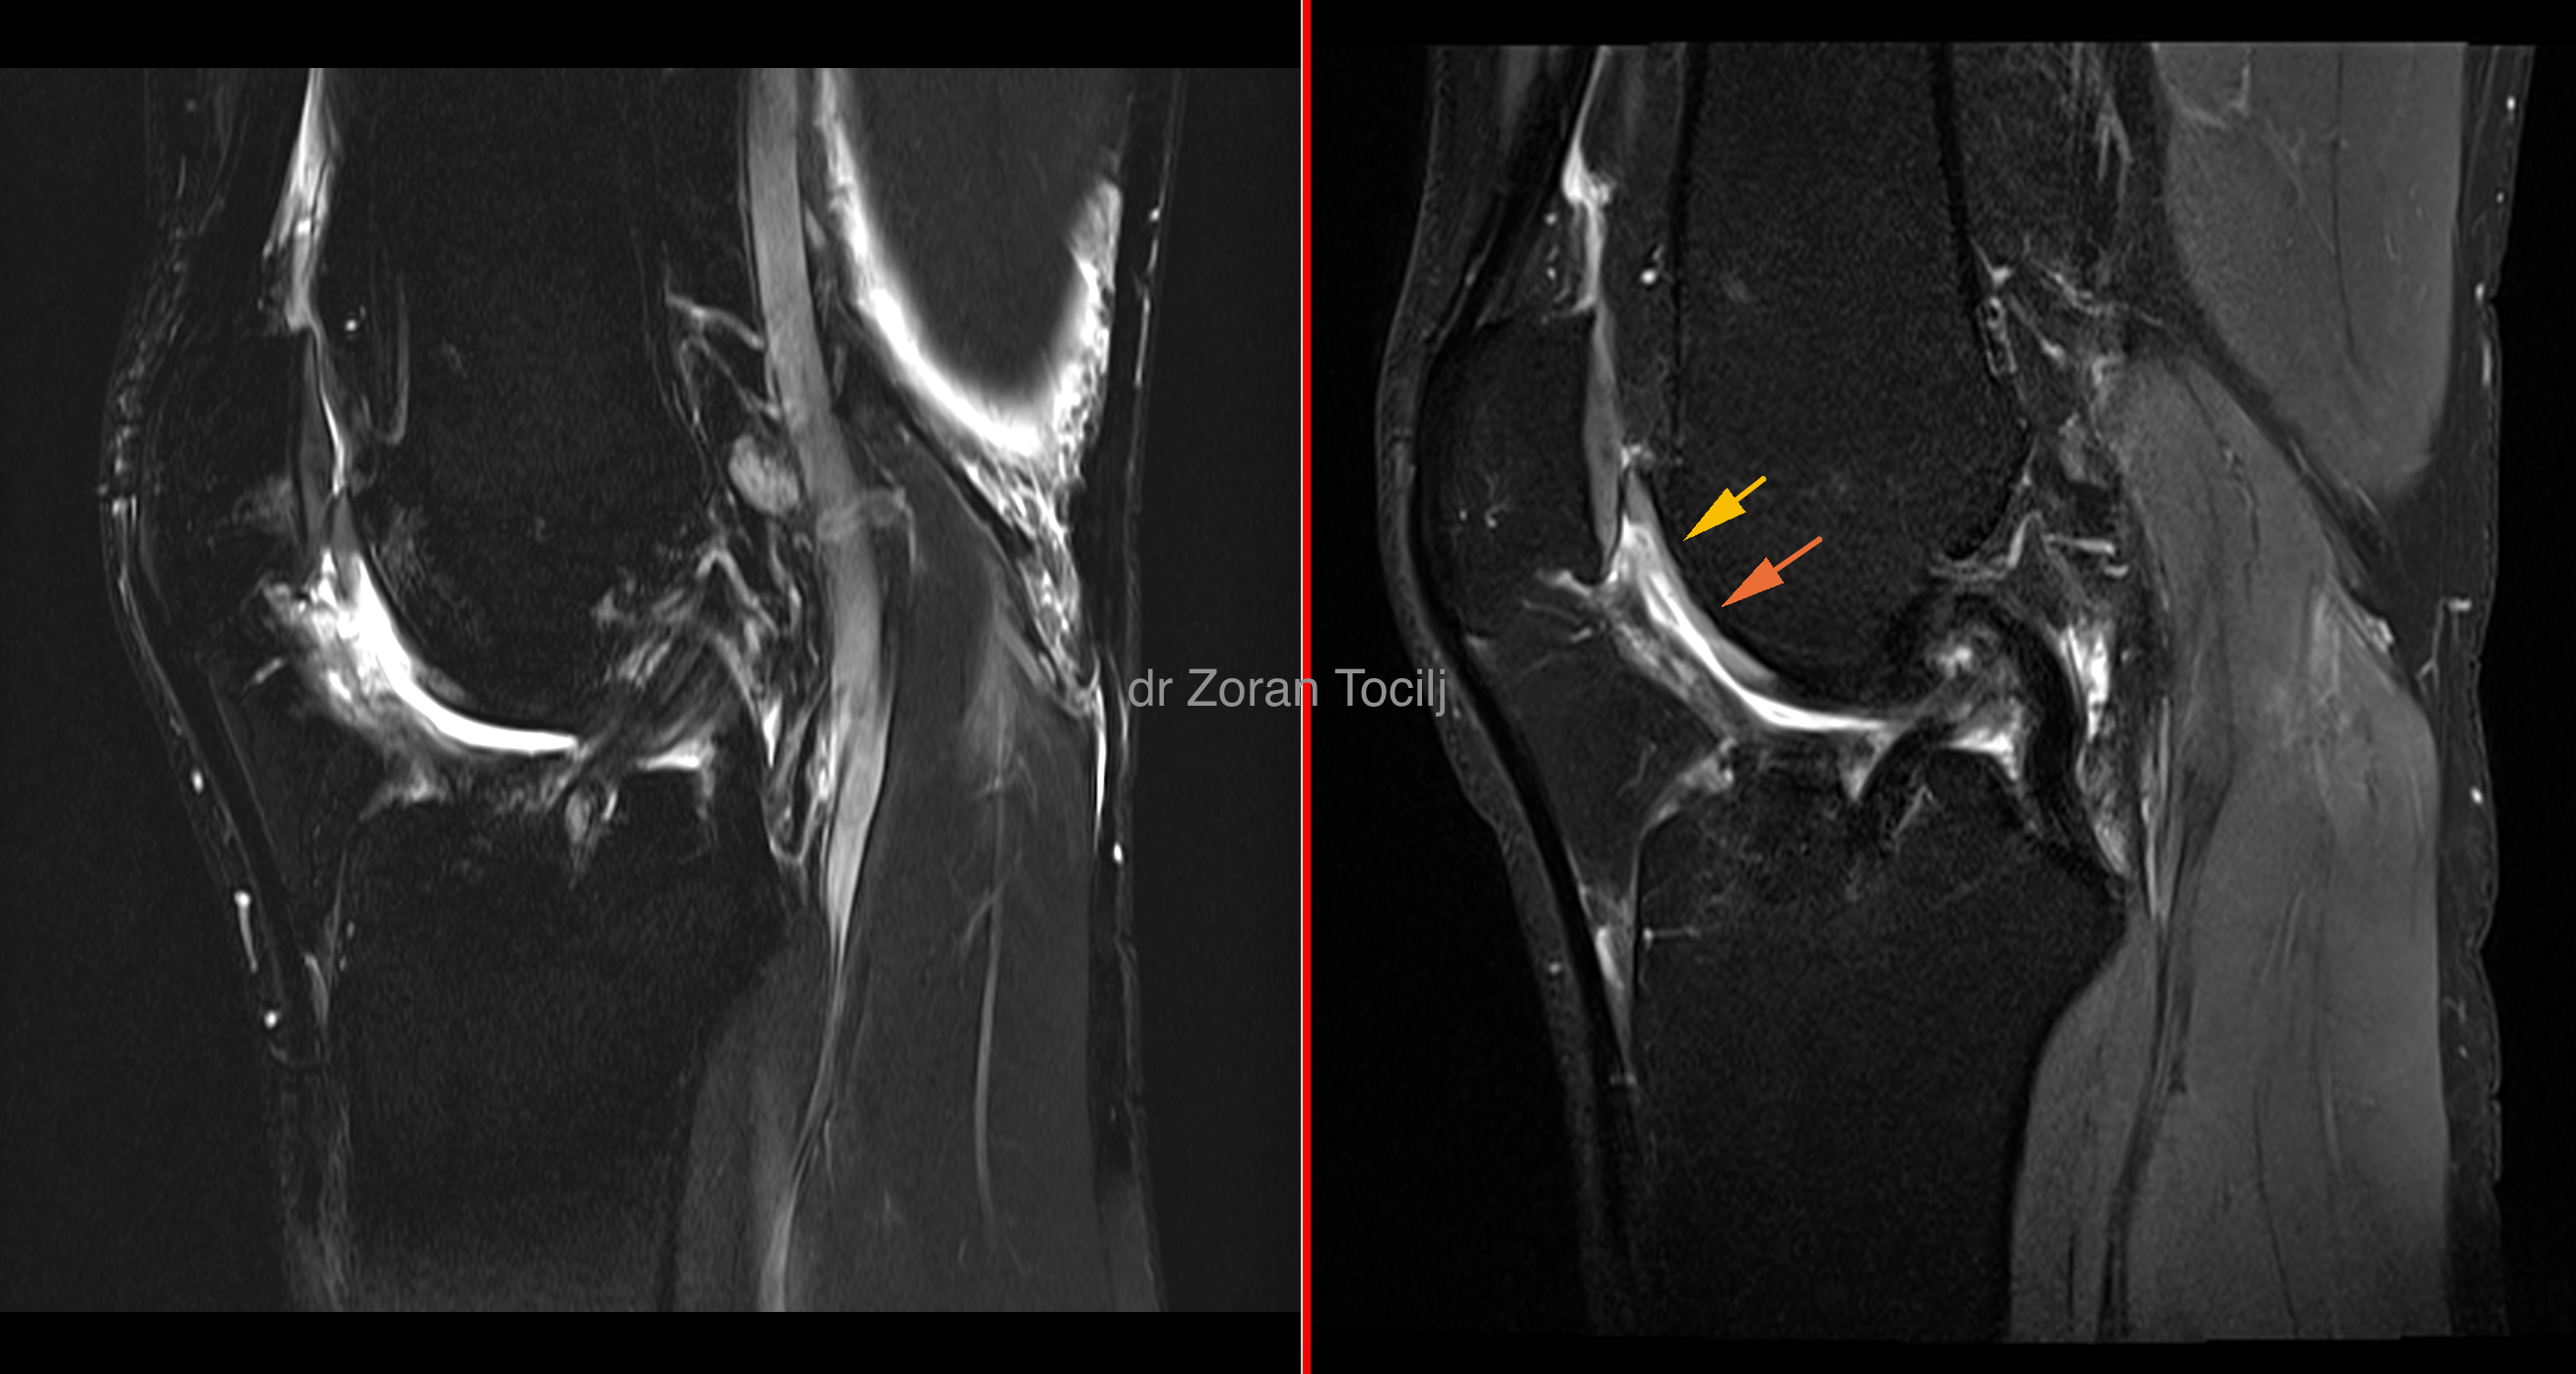

Kneeswell

If the knee starts to inflame, first sign will be swelling up. Swelling up of the knee is a way for body to try to defend it self from the damage by overlubricating the joint and it is a sign that something is not right. Inflamed joint produces cytokines that further promote degrading of the cartilage that induces more inflammation and the vicious circle is started.

Our therapy concentrates on stopping cytokines from doing damage and inducing normal cell metabolism inside the knee. Therapy regenerates inflamed bone tissue so cartilage  can receive enough oxygen to stop cell death and induce good metabolism.  In that positive surrounding, stem cells start to produce basic chondrocytes and that leads to more cartilage matrix being regenerated. The more cartilage the less inflammation, the less inflammation the more cartilage.